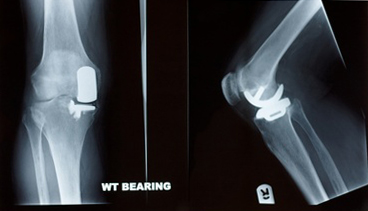

Partial Knee Replacement - Partial knee replacement is a surgery that may be considered for treatment of severe arthritis of the knee. Partial knee replacement allows an orthopedic surgeon to remove only the damaged portion of the knee, leaving the healthy knee intact. Because less of

the knee must be removed, the incision size is smaller, and less tampering with the muscles and tendons occurs. This provides the patient with benefits such as

reduced scarring and reduced post-operative recovery time.

Most often, partial knee replacements use implants placed between the end of the thigh bone and the top of the shin bone. Partial knee replacements can also replace the part of the joint under the kneecap.